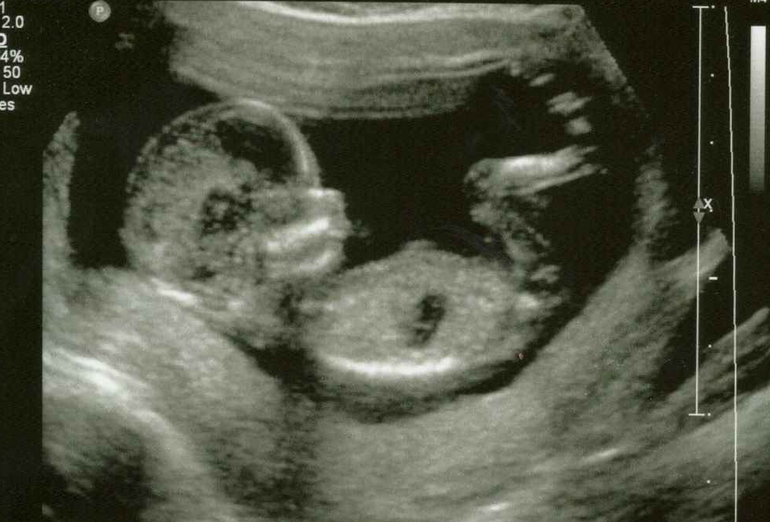

Экватор, отчетыСегодня у нас экватор..несмотря на то что по УЗИ поставили 19 недель и 5 дней..сроки расходятся хоть куда, как и в первую беременность.. Сегодня были на УЗИ все у нас тьфу, тьфу хорошо.. кабася вертится как юла, врач была в шоке от такой активности..

-----------------------------ДЕВОЧКА!!!...да-да -да именно МЫ ждем девочку, нашу доченьку..чему мы безумно рады))

ну и собственно говоря вот наша доченька